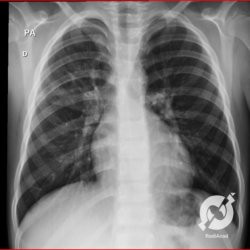

Os agentes etiológicos infecciosos são variados (bactérias, vírus, fungos, parasitas…), mas o que ocorre nos pulmões durante uma infecção por qualquer tipo de agente é a substituição do ar alveolar por secreção (pus, muco, eventualmente sangue ou necrose…) e com isso a manifestação radiográfica vai ser a mesma já que todas estas secreções apresentam a mesma densidade radiográfica: partes moles.

E o nome dado a esta alteração radiográfica que corresponde à substituição do ar alveolar por líquido é a consolidação alveolar.

Uma consolidação alveolar é, por definição, uma opacidade (imagem densa, branquinha) homogênea ou às vezes heterogênea (pela presença de calcificações ou cavidades), de limites mal definidos, exceto quando toca a pleura da parede ou das cissuras pulmonares. É um termo usado tanto em radiografia, como em tomografia computadorizada. Na tomografia, um outro termo é usado: vidro fosco, que é uma opacidade (branquinha mas não tanto como a consolidação), que borra o pulmão mas deixa ver os vasos de permeio (igual bigode de adolescente: dá pra ver todo o fundo).

Nós vamos mostrar aqui um pequeno apanhado de pneumonias de variados agentes, em diversos segmentos e lobos pulmonares, com extensões variadas. O objetivo é identificar o padrão radiológico de consolidação alveolar e não determinar o agente infeccioso, isso vai ser assunto para mais adiante. Aliás já antecipo que é fundamental saber localizar a lesão, porque alguns destes bichos gostam de determinados segmentos, alguns tumores também têm as suas preferências, então localização é fundamental. Se localização não fosse importante, um apartamento na beira do mar sairia o mesmo preço de um apartamento de frente pra BR-101, concordam?

Seguem alguns dos nossos casos de pneumonia para vocês treinarem os olhos e não se apavorarem nos plantões.